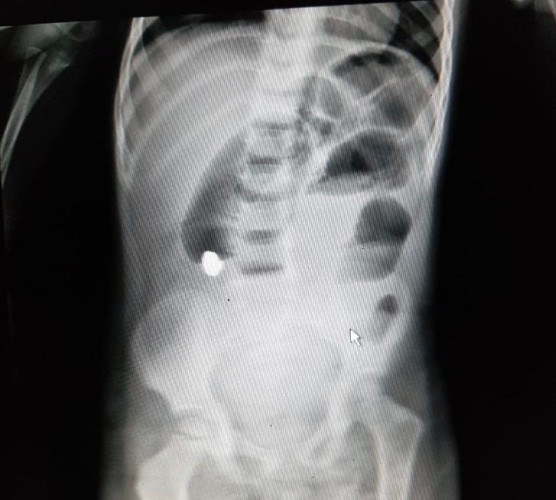

نجح-بفضل الله- فريق طبي بمستشفى الولادة والأطفال بحفر الباطن من إنهاء معاناة طفل كان يشكو من آلام حادة في منطقة البطن ، وبعد إجراء الفحوصات والأشعة الطبية اللازمة ،إتضح وجود جسم معدني مستقر في الأمعاء مسبباً ثقوب وضرر للأمعاء ، وعلى الفور باشر الفريق الطبي بإجراء تدخل جراحي تم من خلاله إستئصال القطعة المعدنية وإزالة الجزء المتضرر من الأمعاء حيث تكللت العملية بالنجاح وغادر الطفل وهو بصحة جيدة ولله الحمد .